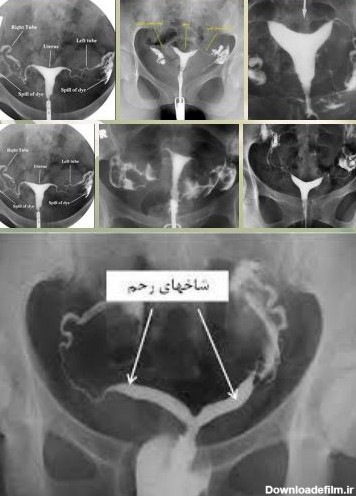

عکس رنگی رحم یا هیستروسالپنگوگرافی نوعی روش تصویربرداری یا رادیوگرافی برای مشاهده رحم و لوله ها است که به وسیله نوعی اشعه ایکس به نام فلو

برای بررسی علت تأخیر باروری، باید سلامت اندامهای تولید مثل مورد ارزیابی قرار گیرند؛ یکی از روشهای تشخیصی که برای بررسی رحم و لولههای رحمی درخواست می شود، هیستروگرافی است. با این تست، پزشک از وضعیت داخلی رحم و لوله های رحمی مطلع میگردد و با توجه به نتایج حاصل از تست، در مورد نحوه درمان تصمیم خواهد گرفت. انجام این تست در ارزیابی ناباروری بسیار مهم است.